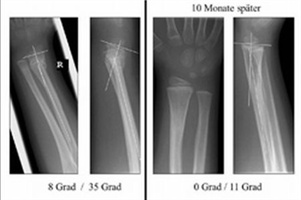

Bei Kindern gibt es eine sehr häufig vorkommende Form der Unterarmfraktur, die möglicherweise am besten von ganz alleine heilt. Und zwar auch dann, wenn sie „abgekippt“ ist und der Knochen schon von außen sichtbar einen Knick aufweist. Diese Erfahrung machen Kinderchirurgen häufig, wenn sie auf die chirurgische Behandlung einer solchen Fraktur verzichten. Trotzdem wird dieser Bruch in der Regel operiert, vor allem dann, wenn die Kinder in der Erwachsenenchirurgie behandelt werden.

Die Kinderchirurgische Klinik der Universitätsmedizin Mannheim (UMM) untersucht nun im Rahmen einer von der Deutschen Forschungsgemeinschaft (DFG) und dem Bundesministerium für Bildung und Forschung (BMBF) geförderten Studie die Hypothese, dass es möglicherweise die sinnvollere Therapie ist, hier auf die selbst korrigierenden Kräfte des kindlichen Körpers zu setzen. Voraussetzung dieser „Spontankorrektur“ ist die Wachstumsfähigkeit des Knochens.

Gegenstand der Studie ist die Fraktur des Unterarms, nahe am Handgelenk, im Bereich der Wachstumszone des Knochens, der so genannten Metaphyse. Die Wachstumsfähigkeit besteht hier bis zum 16. Lebensjahr, zumal die Wachstumsfuge an diesem körperfernen Ende des Unterarmknochens für 80 Prozent des Längenwachstums verantwortlich ist.

Diese Frakturen machen gut ein Drittel aller Knochenbrüche bei Kindern aus. Etwa die Hälfte sind abgekippte Frakturen, bei denen die Knochenfragmente zueinander abgeknickt sind, sich jedoch nicht gegeneinander verschoben haben oder nebeneinander stehen. Im Rahmen der wissenschaftlichen Studie soll untersucht werden, ob sich die klinische Erfahrung, dass sich der abgeknickte Knochen bei Kindern in der Wachstumsphase regelhaft wieder von alleine aufrichtet – also wieder gerade wächst – bei nahezu allen Kindern bestätigt.

Dabei werden die beiden folgenden Behandlungsmethoden miteinander verglichen: Die klassische chirurgische Therapie, bei der der Bruch in Narkose gerichtet und mit einem Metallstift (Kirschner-Draht genannt) fixiert sowie zusätzlich in Gips ruhiggestellt wird. Alternativ wird der Bruch in der abgeknickten Haltung eingegipst. Er verheilt zunächst in dieser Fehlstellung, wächst aber mit der Zeit von alleine wieder gerade.

„Vieles weist darauf hin, dass diese Art der Therapie – der Verzicht auf eine Operation – absolut sinnvoll ist. Der Beweis soll mit dieser randomisierten Studie erbracht werden. Die Studie hat das Ziel, Sicherheit zu erlangen und damit auch eine Entscheidungshilfe für die Wahl der geeigneten Behandlung zu erhalten“, so der Kinderchirurg Professor Wessel.